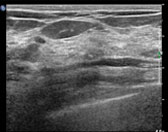

유방초음파

The center utilizes advanced techniques for breast cancer diagnosis, such as fine-needle aspiration cytology, stereotactic biopsy, and Mammotome biopsy, which enhance both diagnostic accuracy and the success rate of tumor excision. Once breast cancer is confirmed, various tests are performed to determine the cancer stage. Using PET, MRI, whole-body bone scans, and chest/abdominal CT scans, the center accurately evaluates metastasis and determines the patient’s preoperative cancer stage.